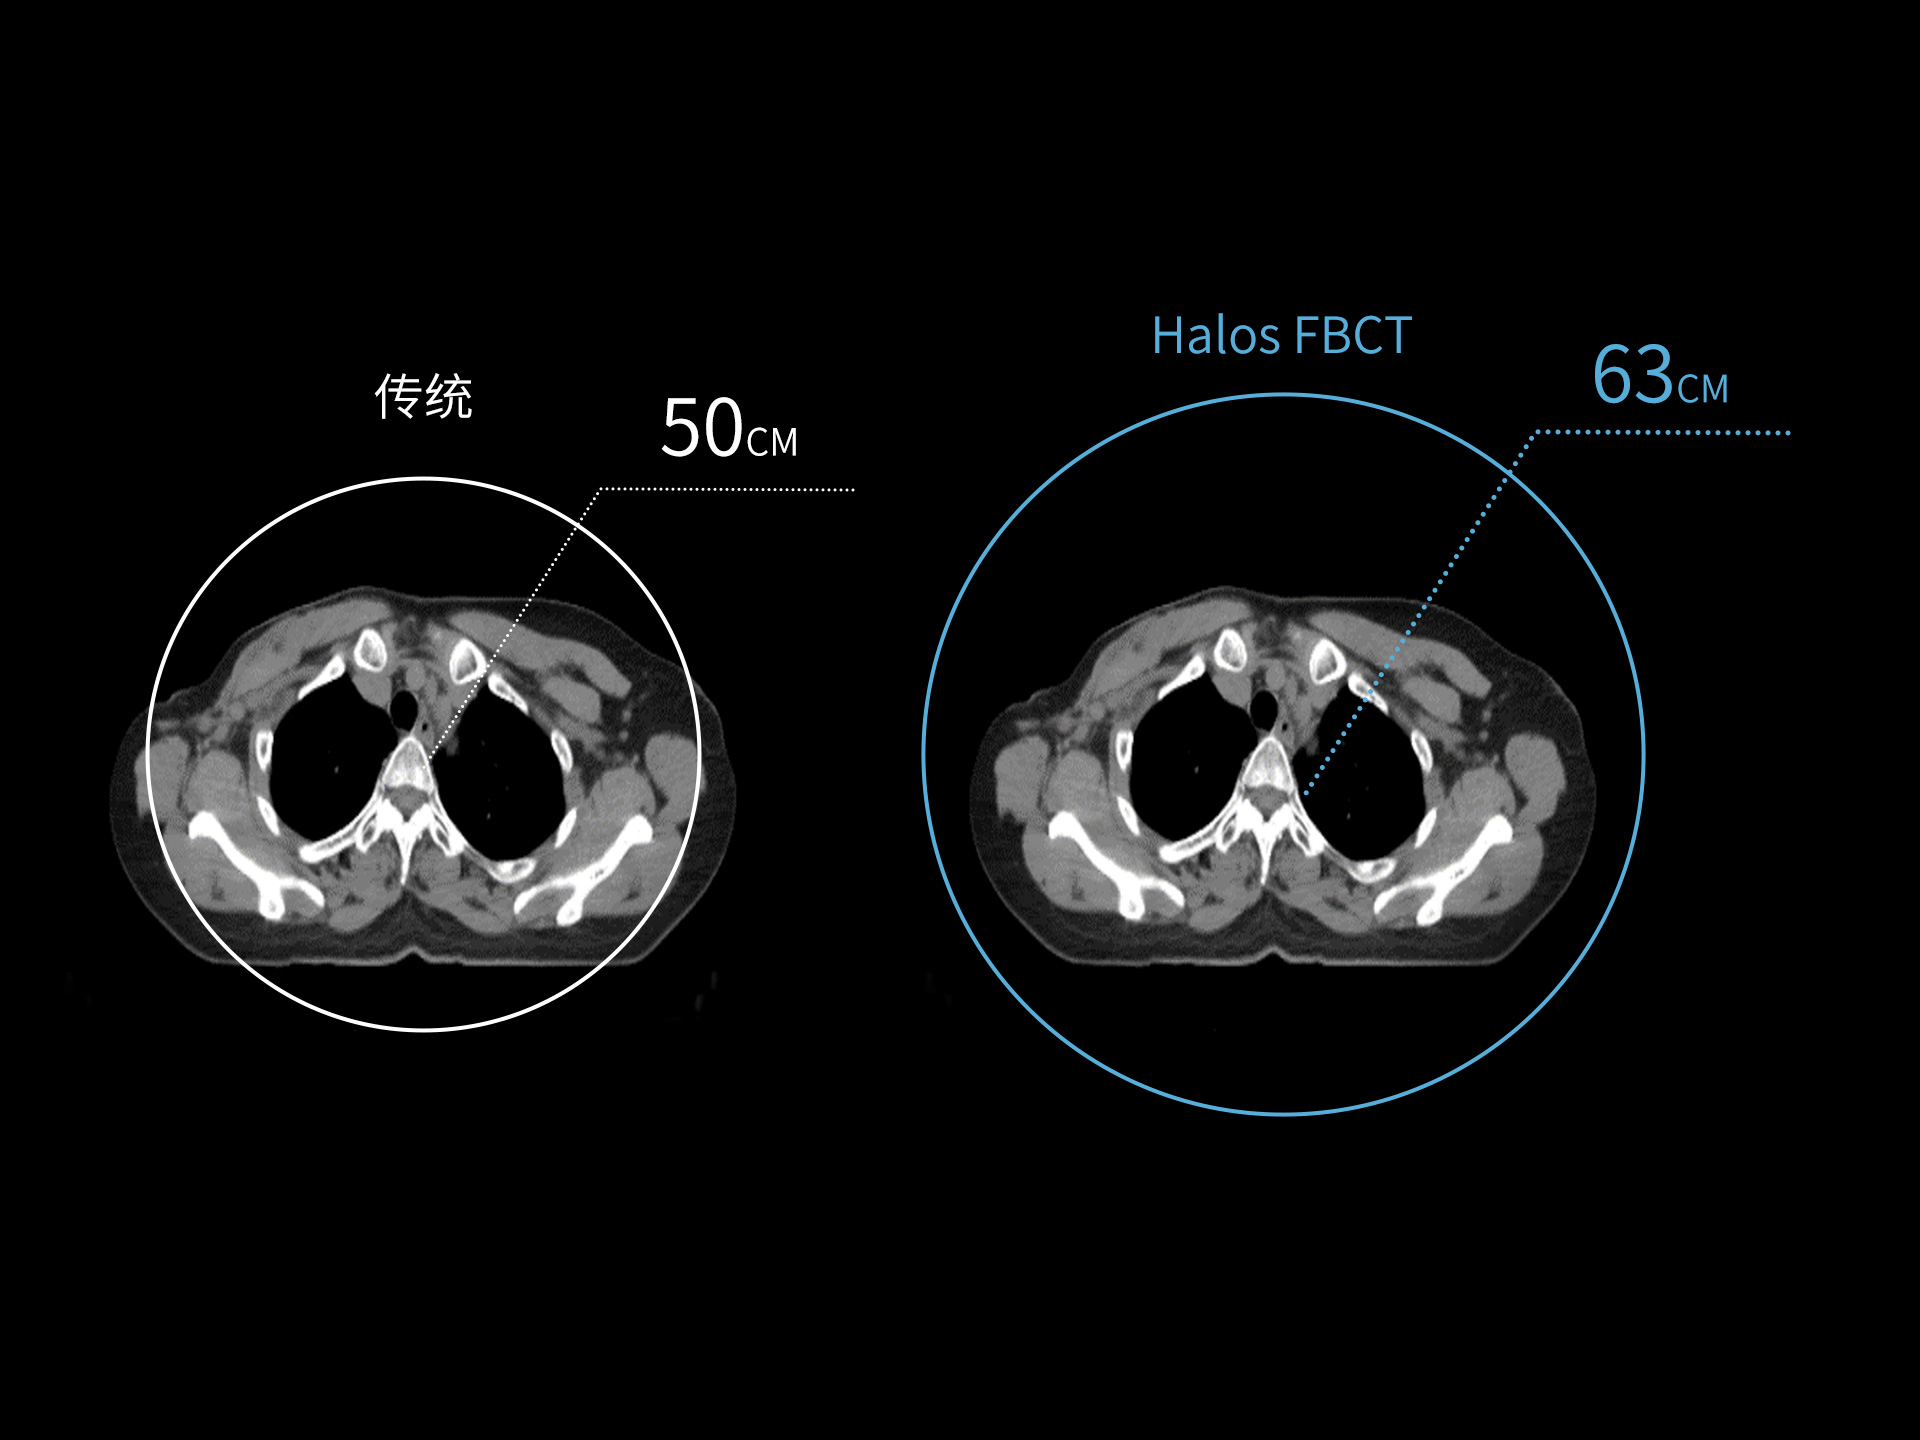

标准视野 63cm,避免扫描信息缺失